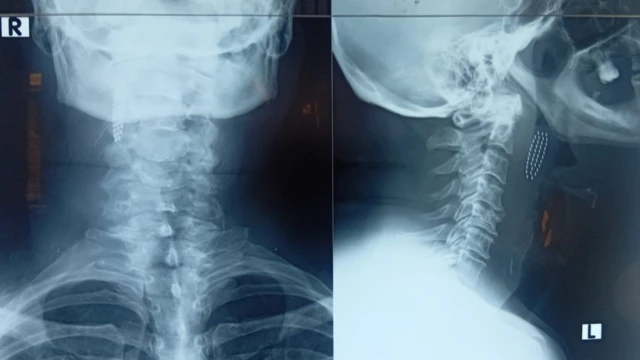

ඒ අනුව, ඔහු X-Ray පරීක්ෂණයකට භාජනය වී තිබුණු අතර එම වාර්තාව අනුව ස්ථිරව ම දත් බුරුසුවේ හිස කොටස ඔහුගේ ශරීරය තුළ ඇති බවට තහවුරු විය.

"හරියට කණ්ණාඩියෙන් මූණ බැලුවා වගේ, X Ray එකේ පේනවා බුරුසුව උගුරේ තියෙනවා කියලා. මාතර හොස්පිටල් එකෙන් කිව්වේ ප්ලාස්ටික් X Rayවලට අහුවෙන්නේ නැහැ කියලා," ඔහු පැවසීය.

අනතුරුව විශේෂඥ වෛද්ය අනුරුද්ධ වික්රමසිංහගේ උපදෙස් පරිදි යළිත් X-Ray පරීක්ෂණයක් සිදු කර තිබුණු අතර එහිදී තවමත් කැඩී ගිය දත් බුරුසු කොටස ඔහුගේ ශරීය තුළ ඇති බව යළිත් තහවුරු කර ගැනිණි. අනතුරුව තවත් CT පරීක්ෂණයක් සිදු විය.

විශේෂඥ වෛද්යවරයාට අනුව, දත් බුරුසුවේ හිස කොටස ප්රේමලාල්ගේ ආහාර ජීර්ණ පද්ධතිය සහ ශ්වසන මාර්ගයට පොදු කුටීරය වන ග්රසනිකාවට ද (pharynx) හානි කරමින්, ඉන් පිටතට ගොස් ඔහුගේ ගෙළේ ඇති ප්රධාන ලේ නහරය අසල (common carotid) නතර වී තිබිණි.